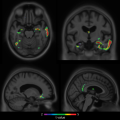

La physique dans les profondeurs du cerveau

Vie et Terre